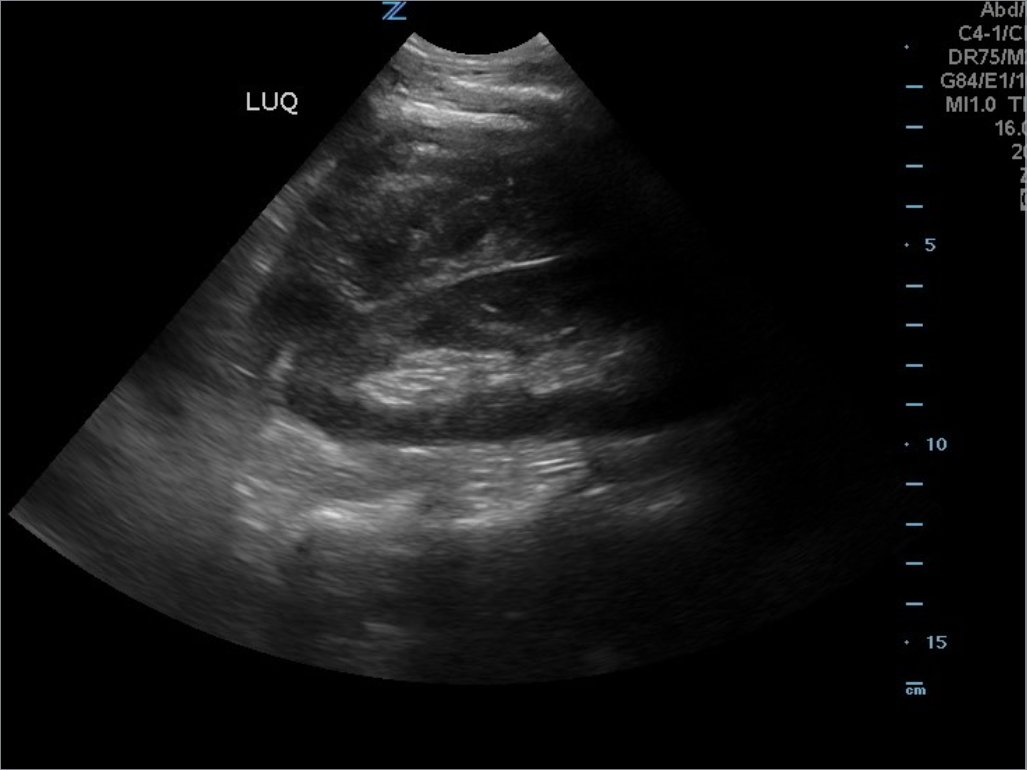

A 49-year-old male presents for evaluation of hematuria and left flank pain after mechanical fall down stairs four days ago. Point-of-care ultrasound (POCUS) focused assessment with sonography in trauma (FAST) exam demonstrated subcapsular renal hematoma. Once a subcapsular hematoma is recognized the provider should keep in mind that this condition may be managed conservatively in patients with two normally functioning kidneys, but may require urgent intervention if the patient is at risk for significant renal disease, such as a single kidney. The use of bedside ultrasound can expedite diagnosis and care for these patients, and allow proper consultants to be contacted early. Some consultants that may need to be consulted include nephrology, urology, and/or internal medicine. This case report emphasizes the utility of the FAST exam for patients presenting for non-acute trauma. The FAST exam can be utilized not only to identify free fluid in the abdomen and pelvis but also to visualize organs and the surrounding tissues for abnormalities after a trauma.